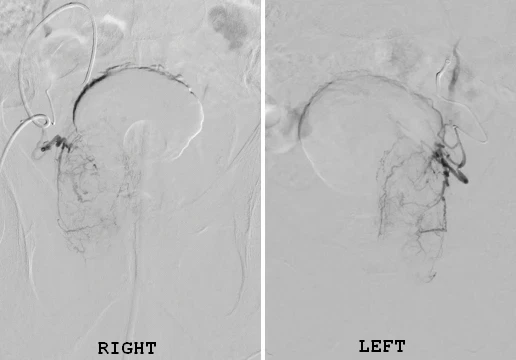

Prostate artery embolization is performed through a small puncture in the wrist or groin, not through the urinary passage. Under real-time imaging guidance, a thin catheter is navigated to the arteries supplying the prostate. Tiny embolic particles are then delivered to selectively reduce blood flow.